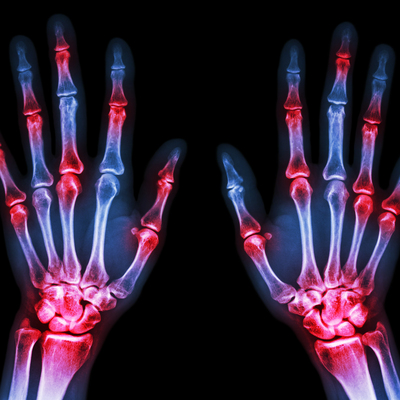

Eklemde, oynak yerlerinde ağrı, şişlik, sabah katılığı-tutukluğu, ısı artışı bazen de kızarıklık olabileceğini aktaran Şahin, şöyle devam etti: "Bunların ayırıcı tanısının yapılması son derece önemlidir. Örneğin; özellikle bölgemizde sıklıkla karşımıza çıkan Ailesel Akdeniz Ateşi (FMF) hastalığı erken yaşlarda belirti vermektedir. Hastalar, tekrarlayan eklem iltihabıyla bize başvurmaktadır. Tanısında hastanın klinik bulguları, aile öyküsü oldukça önemlidir. Bu hastalıkta olduğu gibi bazı romatizmal hastalıklarda, bazı nedenlerden dolayı halen tanıda gecikme yaşanmaktadır."

Vücudun kendi kendine saldırdığı romatizmal hastalıklarda tekrarlayan iltihap ataklarının yaşandığını vurgulayan Şahin, "Bu hastalıkların erken tanısında son yıllarda ultrasonografi, tırnak yatağı kapillaroskopisi, tükürük bezi biyopsisi, cilt-kas biyopsileri ve çeşitli diğer doku biyopsileri gibi işlemler yapılıyor. Erken tanı koyup tedaviye başlamak, birçok romatolojik hastalıkta sakatlık ve iş gücü kaybını önlemede önemlidir" ifadelerini kullandı.